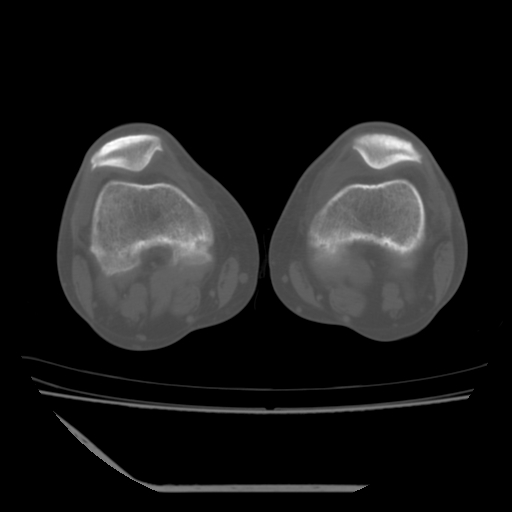

标题: CT13225:老年男性,左膝关节疼痛数月;请各位老师讨论。 [打印本页]

标题: CT13225:老年男性,左膝关节疼痛数月;请各位老师讨论。

骨质增生,骨性关节面硬化,关节积液,考虑退行性骨关节病

关节腔内少量积液,关节面退变。

双膝退变

骨质增生,骨性关节面硬化,关节间隙失常,关节积液,考虑退行性骨关节病.

骨质增生,骨性关节面硬化,关节积液,考虑退行性骨关节病。

这是由于两侧的肌肉不对称所致,加上扫描的平面也有些差异。请看示意图:

这个病例诊断:退行性骨关节炎